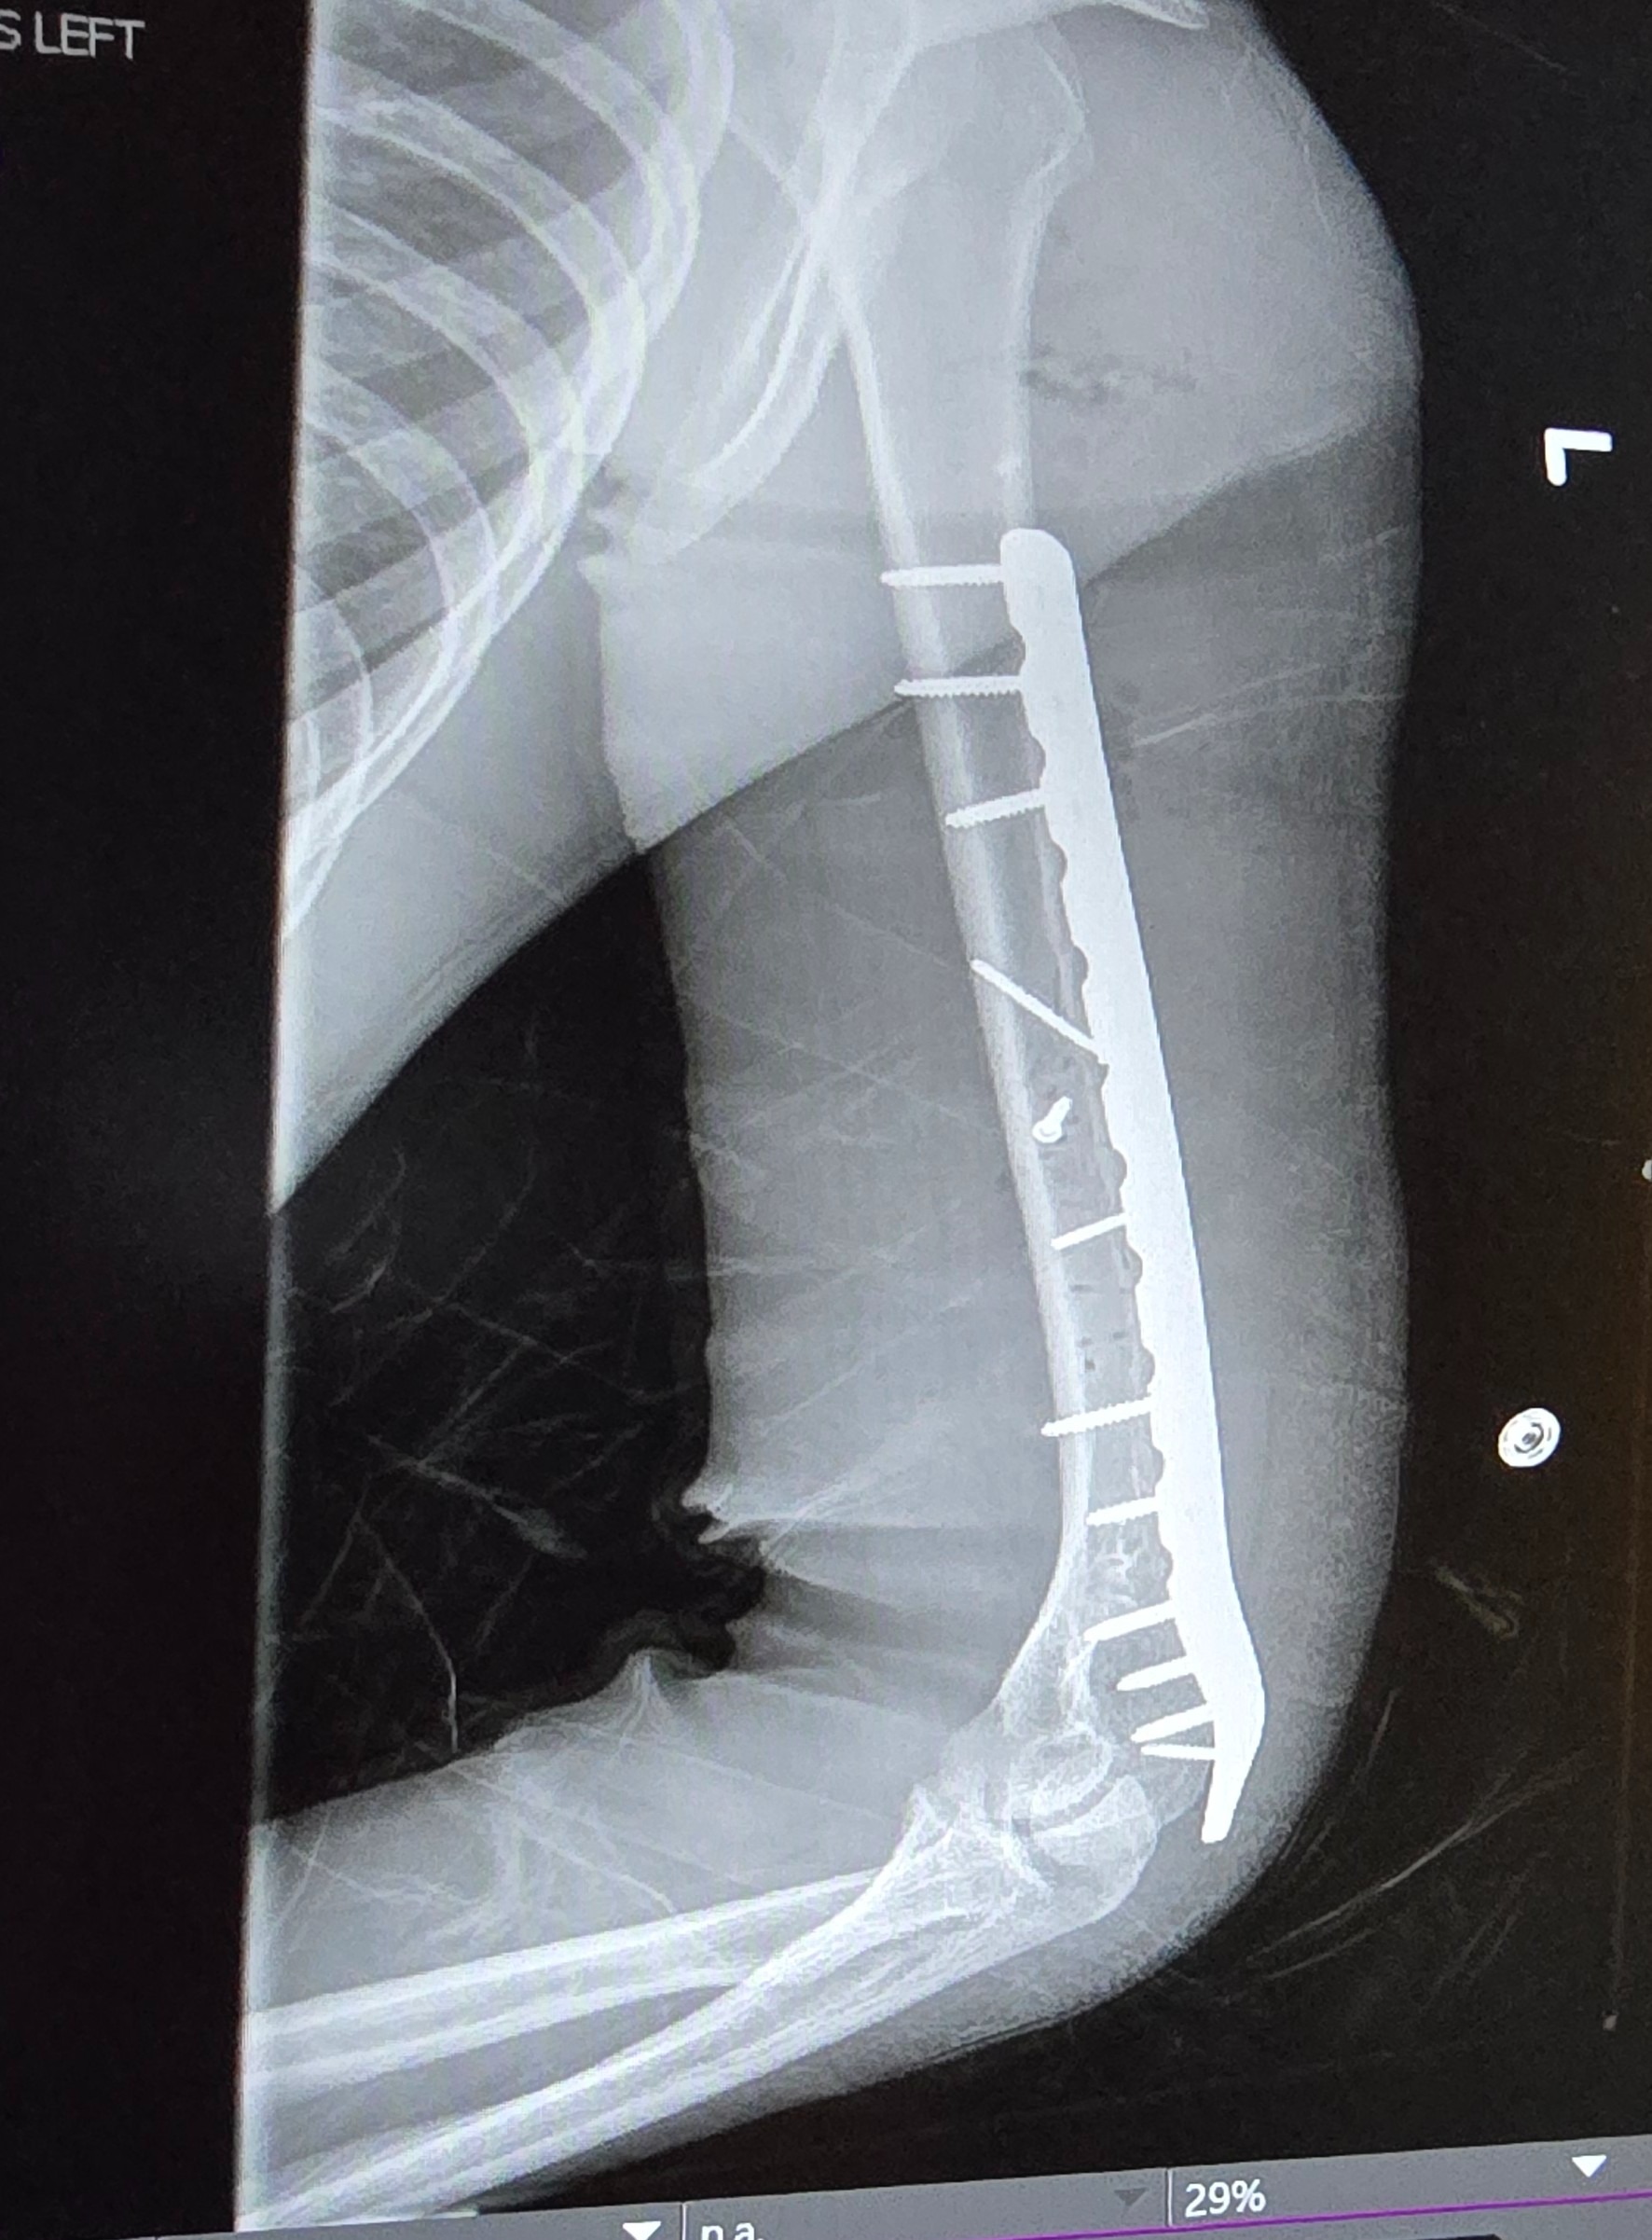

Even though he was wearing his seatbelt, the entire impact hit his left side. His left arm was shattered into multiple pieces, causing severe nerve damage. His left femur was broken into three pieces. He also struck his head against the window.

He was rushed to the hospital, where he spent a long night in unbearable pain before undergoing nearly eight hours of emergency surgery the next morning. Surgeons worked tirelessly to reconstruct his arm and leg. Today, Cole lives with metal rods and screws permanently placed in both his arm and leg.